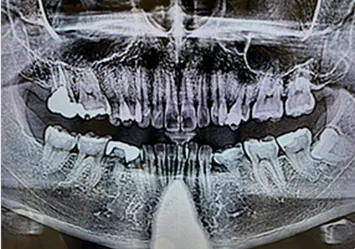

1 歯科用CTなどを活用した正確な診査診断

インプラント治療成功のポイントは「口腔衛生環境」、「身体の健康状態」、「骨の状態(骨の幅、深さ、密度)」、「インプラントの埋入位置」、「担当するスタッフの技術や評判」、「院内の衛生環境」等様々あります。

当院では、歯科用CTによる一般的なレントゲン写真よりも高い精度での検査により、患者様の顎の状態を詳細に把握することで、手術の成功率を高めるとともに患者様の治療時と治療後の痛みの軽減にも役立ちます。

歯科用CT 恵比寿南DENTAL

歯科用CT

歯科用CTは、従来の2次元のレントゲン装置とは異なり、3次元の立体画像を撮影可能にする装置で、精度の高い診査診断検査や精密歯科治療を行う際には欠かせない機器です。

従来の2次元のレントゲン撮影による画像では見ることができない口腔内を3次元的に把握できることで、歯や歯周組織、顎の骨やその中にある神経や血管の位置まで正確に把握することができます。

当院では、歯科用CTを完備しておりますので、歯周病治療、根管治療、インプラント治療や親知らずの抜歯など、精度の高い診査診断が求められる治療も安全に受けて頂けます。